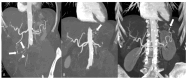

Systemic vasculitides are a rare and complex group of diseases that can affect multiple organ systems. Clinically, presentation may be vague and non-specific and as such, diagnosis and subsequent management are challenging. These entities are typically classified by the size of vessel involved, including large-vessel vasculitis (giant cell arteritis, Takayasu's arteritis, and clinically isolated aortitis), medium-vessel vasculitis (including polyarteritis nodosa and Kawasaki disease), and small-vessel vasculitis (granulomatosis with polyangiitis and eosinophilic granulomatosis with polyangiitis). There are also other systemic vasculitides that do not fit in to these categories, such as Behcet's disease, Cogan syndrome, and IgG4-related disease. Advances in medical imaging modalities have revolutionized the approach to diagnosis of these diseases. Specifically, color Doppler ultrasound, computed tomography and angiography, magnetic resonance imaging, positron emission tomography, or invasive catheterization as indicated have become fundamental in the work up of any patient with suspected systemic or localized vasculitis. This review presents the key diagnostic imaging modalities and their clinical utility in the evaluation of systemic vasculitis.